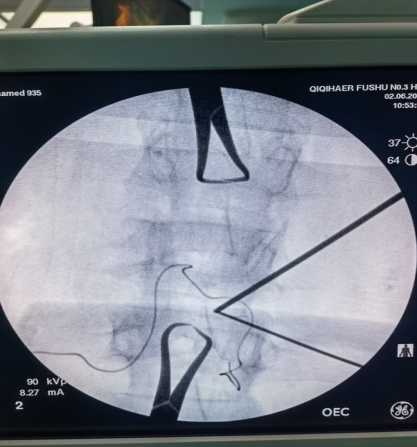

术中穿刺针透视定位